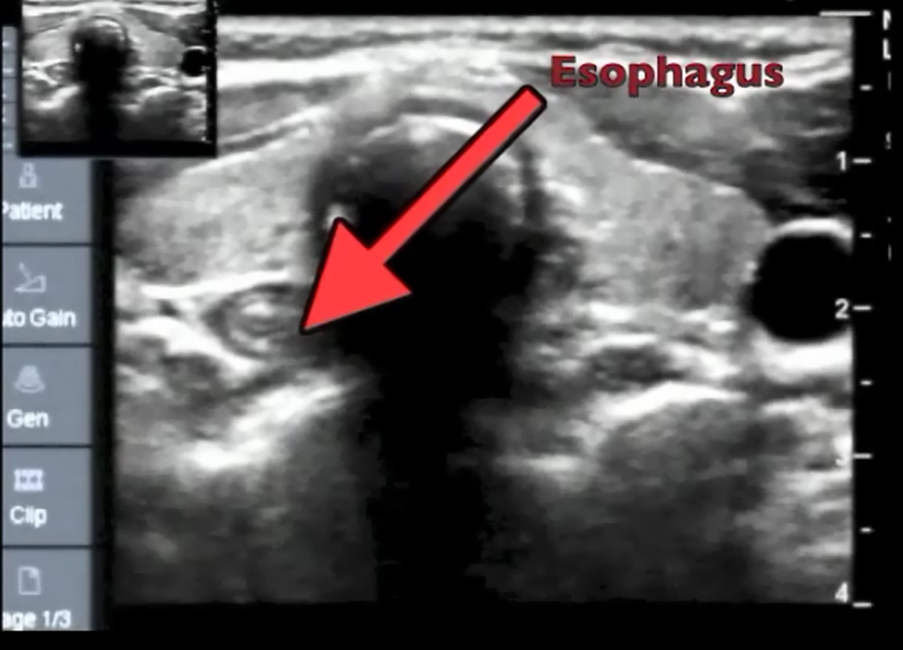

You might not even need to manipulate the larynx for that better view..because you can image the airway anatomy externally and display on a monitor and know exactly where you need to move the ETT to pass the cords!

Its not a blind technique it is an ultrasound enhanced technique of intubation!